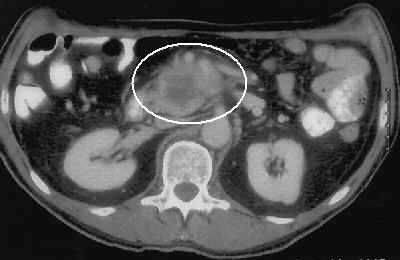

CT cancer: ab , c, d, e, f        CT of a resectable case, more CT and more CT